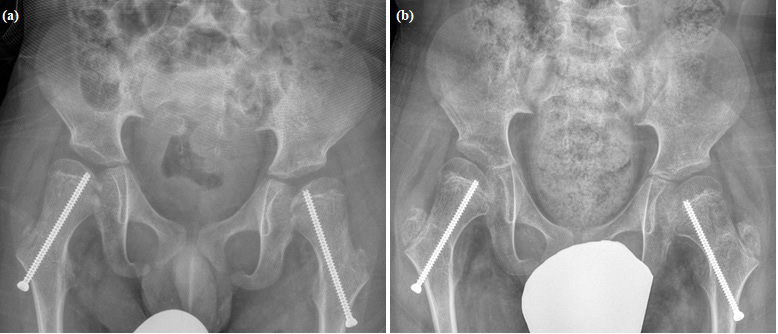

Figure 5: (a) Boy GMFCS 4, 8 years old, directly after the operation. Screw location relative to middle of epiphysis and trochanter not important. Enough windings of screw need to fix epiphysis. (b) Boy GMFCS 4, 19 months after surgery. Clearly recognizable varus tilt of the femoral neck and epiphyseal plate. Screws only briefly hold epiphyseal joints.

figure 5